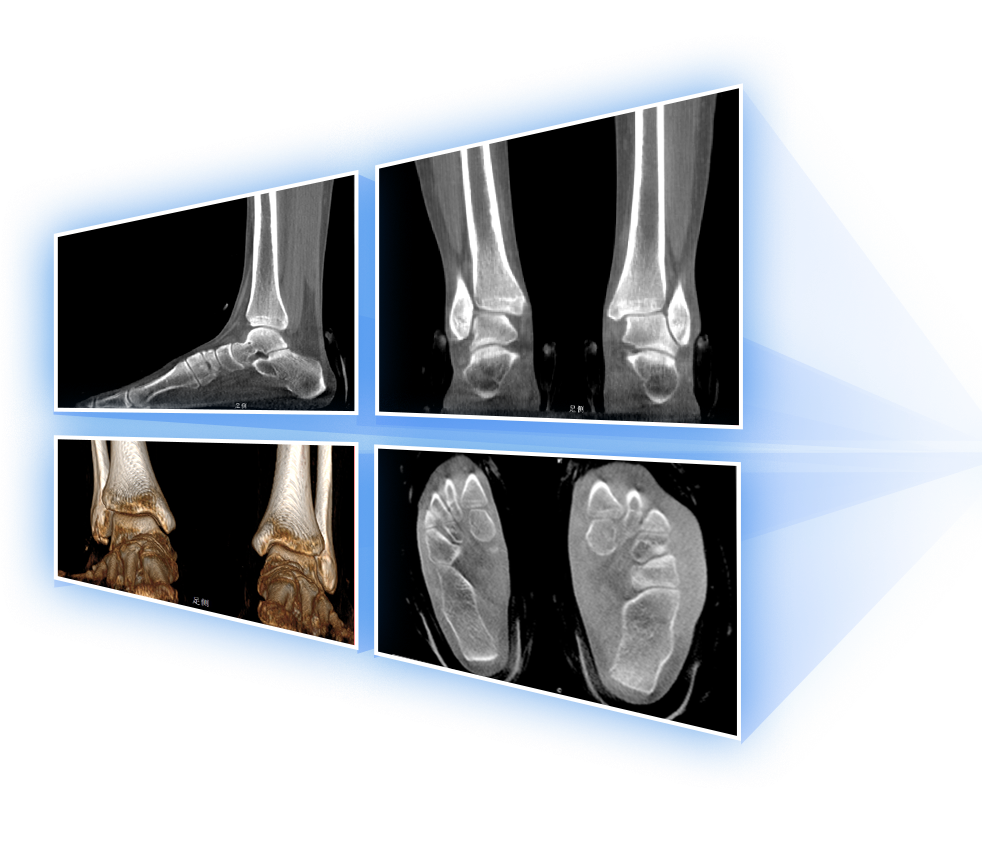

獨特的負重位三維影像

填補常規(guī)CT/MR空白

助力術(shù)前規(guī)劃和術(shù)后評估

獨特的負重位三維影像

足踝

2D+3D一站式快速檢查